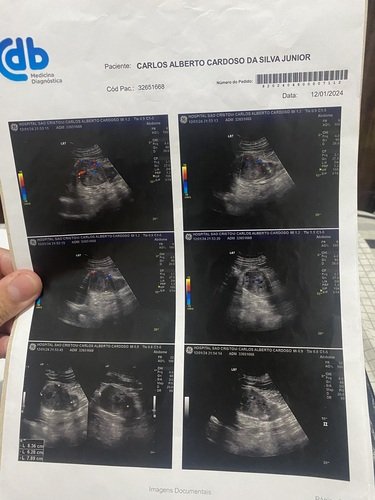

A alguns dias atrás fui diagnosticado com um cancer no rim, após exames, ultrassom, tomografia, o exame mostrou que ja tomou 90% do rim, alternativa médica e a retira do Órgão com urgência, pois trata-se de um câncer maligno . Pelo sistema público pode tratar da demora de 90 dias, não tenho esse tempo para aguentar.

Tenho todos os laudos exames que já foi realizado.